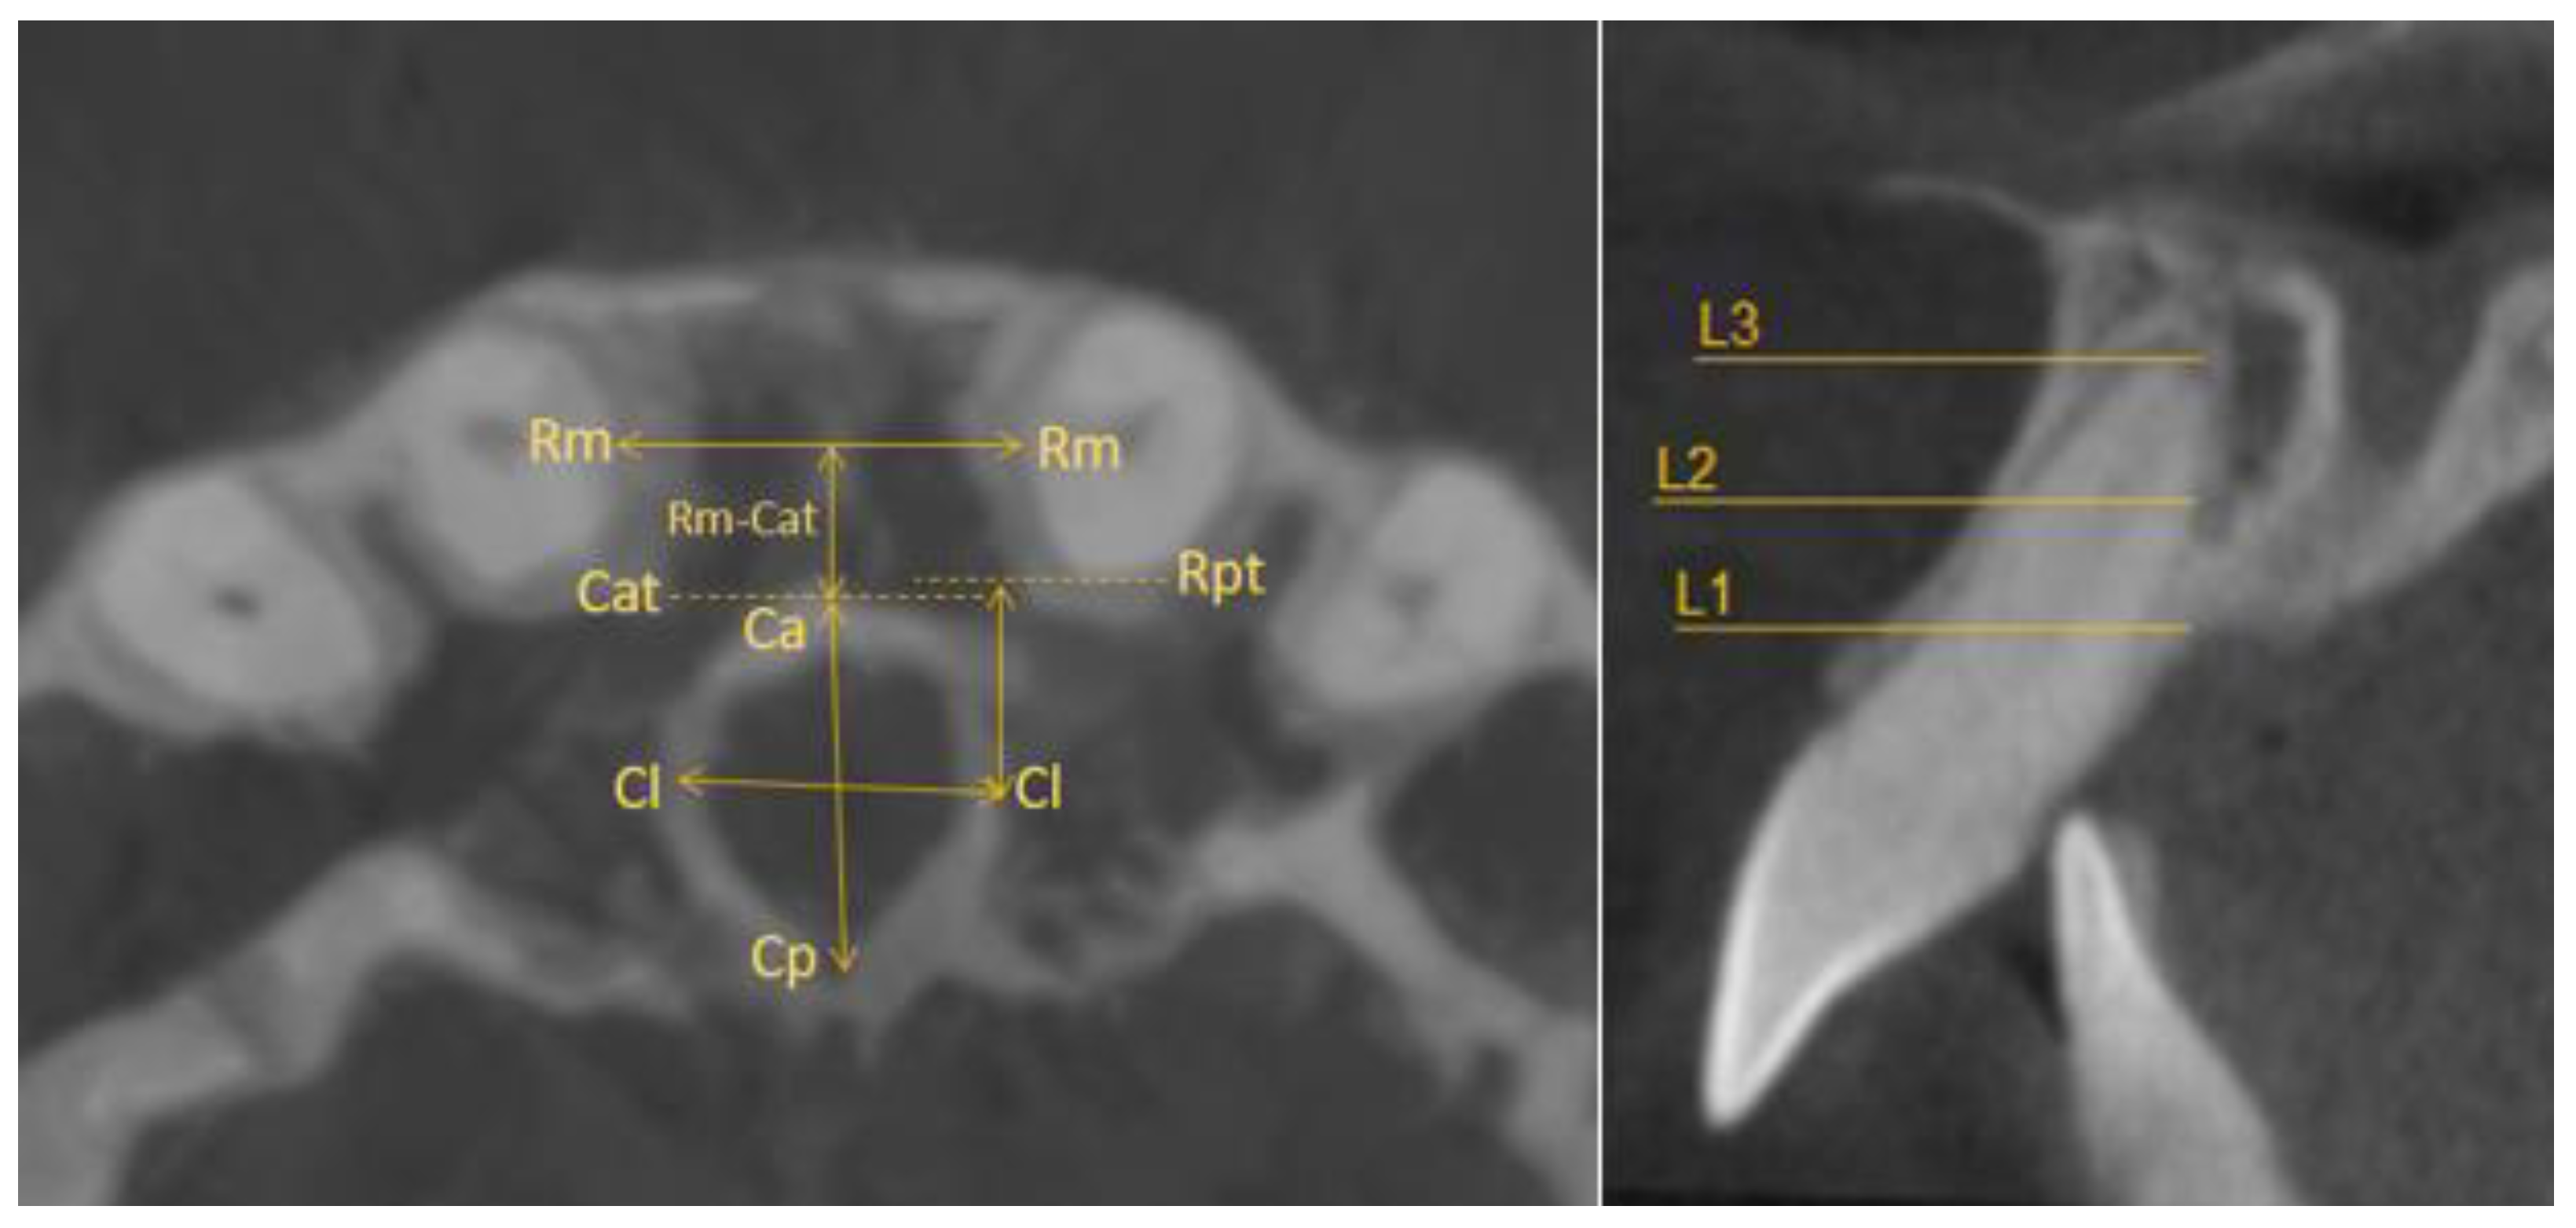

- Horizontal plane separately for each level—L1, L2, and L3:

- Incisive canal width—|Cl-Cl|.

- Antero-posterior IC—|Ca-Cp|.

- Distance between the most mesial point of the root and the tangent passing through the most anterior point of the incisive canal—|Rm-Cat|.

- Distance from Cl to the posterior edge of the incisor root—|Cl-Rpt|.

- Distance between roots |Rm-Rm|.

- Coronal plane:

- Angle formed by the long axes of the central incisors (values above zero for convergent roots, negative values for divergent roots).